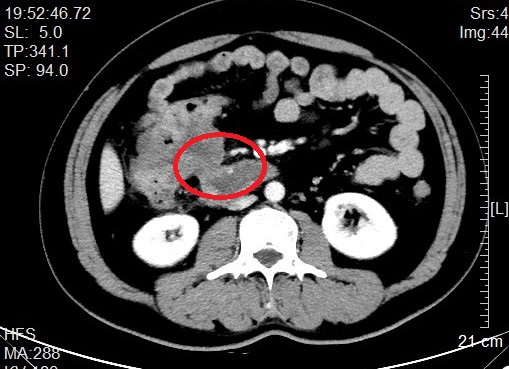

来自省内正值中年的邹先生和张先生都因“阵发性腹痛不适感”就医而发现结肠肿瘤,慕名转诊找到我院治疗。杨春康教授接诊,经过详细全面的检查后,发现二者的病情相似,都为升结肠近肝曲部的肿瘤且肿瘤已侵犯临近的重要脏器——十二指肠,全身其他部位没有发现肿瘤转移病灶,属于局部晚期病例。面对仍有治愈希望的病人以及家属的殷切希望,尽管病情高度复杂,手术风险和压力巨大,杨春康教授和他率领的医疗护理团队没有在困难面前退缩。在与病人及家属充分沟通后,决定为他们手术,并制定周密的手术方案。